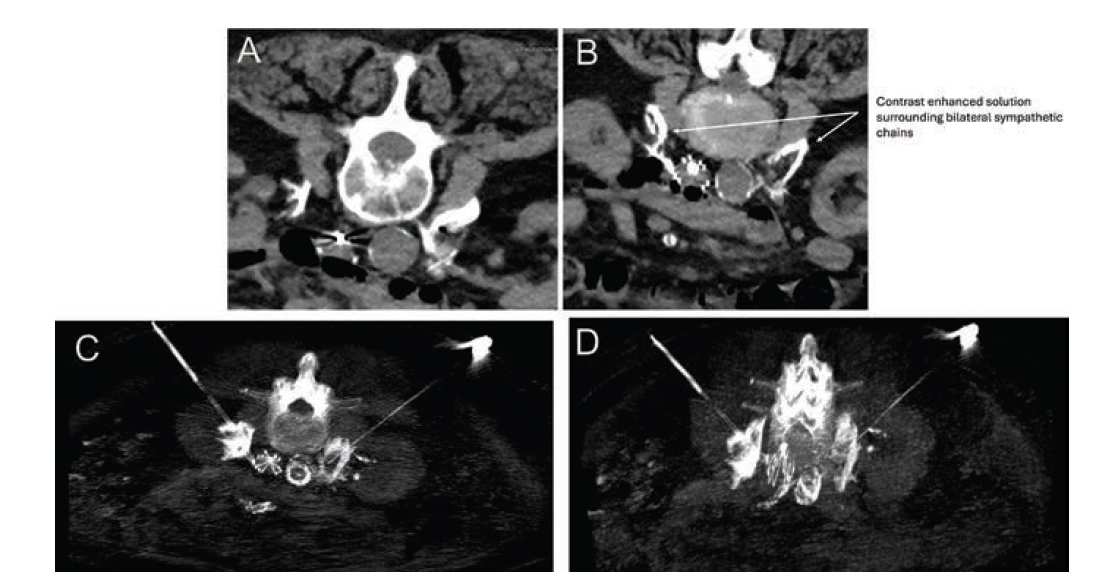

In brief, the procedure was initiated by obtaining intravenous access to provide moderate sedation. The patient was placed prone in the CT scanner (Brilliance iCT 256 [Phillips]). Minimal procedural medications were administered: two 25-µg doses of intravenous fentanyl and 4 mg of intravenous ondansetron. Initial CT (3-mm width slices) images were obtained from the diaphragm to the pelvis. The access site was cleaned and prepped under sterile conditions, and 1% lidocaine was used for subcutaneous anesthesia in the paralumbar region. Access sites were chosen that provided a safe path to the bilaterally lumbar sympathetic chains at the L2/L3 level. An oblique needle path was required to avoid vital structures.

Under intermittent CT guidance, two 22G needles were advanced lateral to the iliopsoas muscles until the tips were immediately adjacent to the sympathetic chains. Needle placement was confirmed by an inability to aspirate blood and by a test injection of 4 cc of a 10% contrast (Omnipaque 350 [GE Healthcare]) saline mixture, which confirmed spread around the bilateral sympathetic chains. Subsequently, 2.5 mL of 99% ethanol was administered on each side, with a dwell time of 3 minutes. This was followed by an injection of a mixture containing 3 mL of betamethasone acetate/betamethasone sodium phosphate (Celestone Soluspan), 4 mL of 0.5% of bupivacaine, and 1 mL of Omnipaque 350 contrast, which diluted the original ethanol injection. Post-injection CT imaging confirmed that the solution surrounded the bilateral lumbar sympathetic chains (Figure 4). The patient tolerated the procedure well without any complaints of pain or changes in vital signs. She was transported to the recovery area without complications. Total procedure time was 21 minutes; administered radiation was DLP1499 mGy.cm, CTDIvol 16.3 mGy.